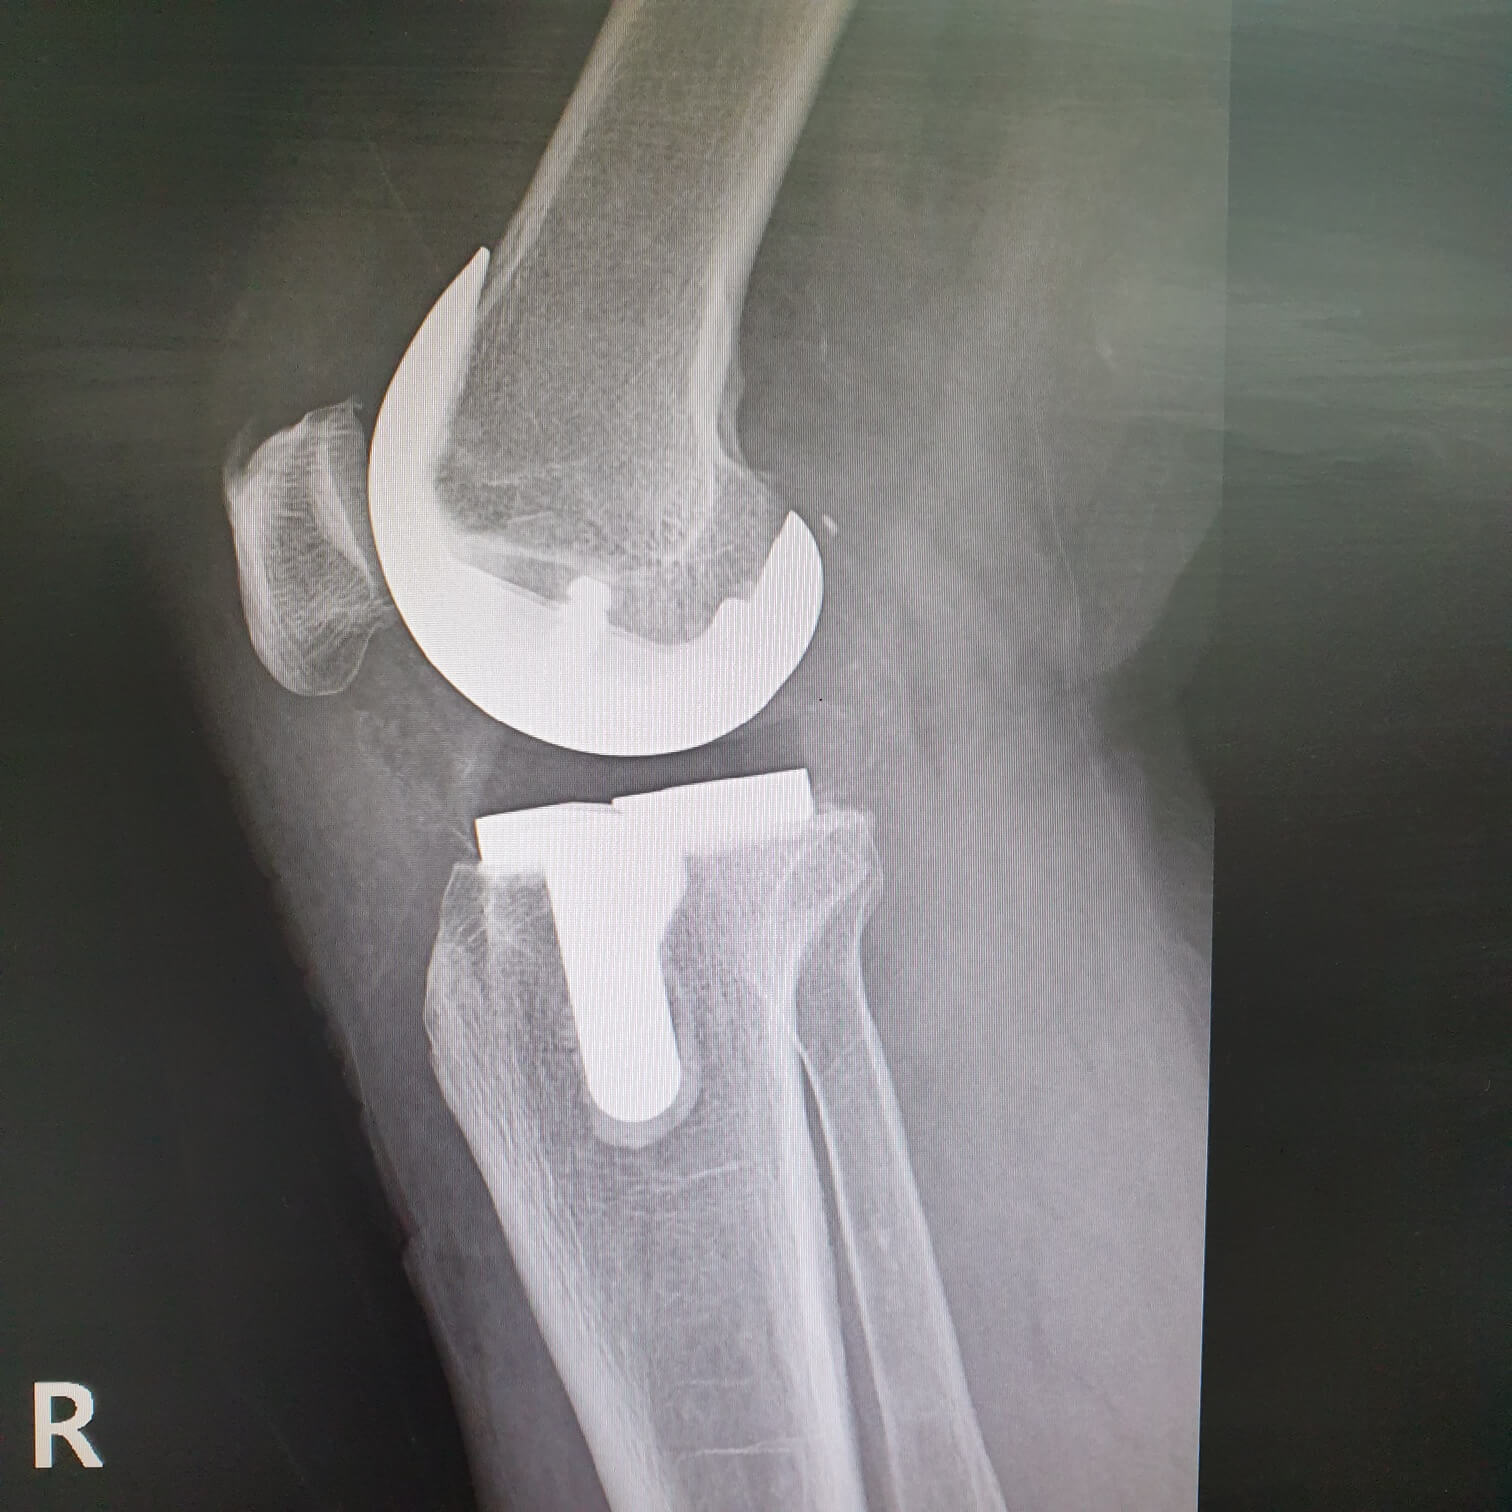

슬관절 인공 관절 치환술은?

무릎의 퇴행성 관절염이나 류마티스 관절염으로 인해 관절이 파괴 된 경우 관절 연골과 뼈를 제거하고 관절 표면을 금속 삽입물과 고밀도 플라스틱으로 교체 삽입하는 수술을 말합니다.